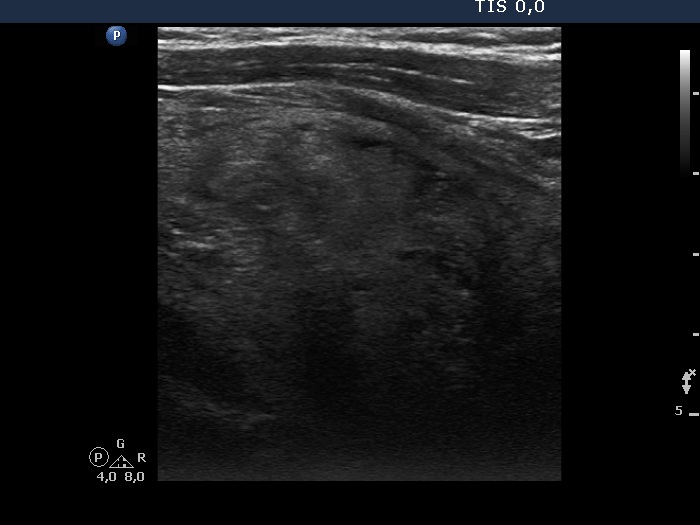

Right lobe, longitudinal scan

Right lobe, longitudinal view. The lobe has very low proportion of nurmal tissue.